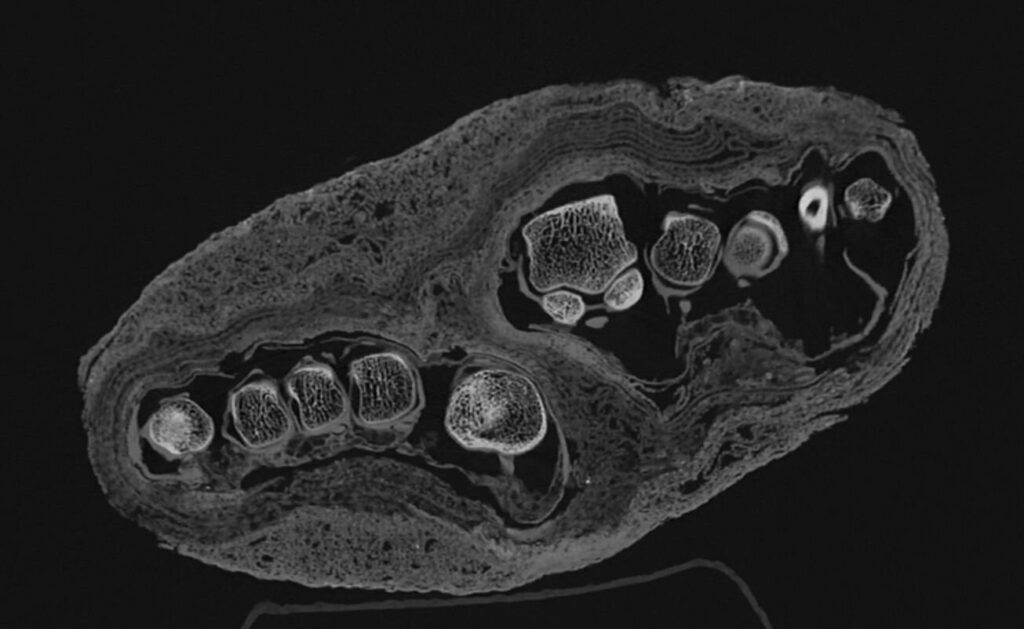

One of the most remarkable aspects of the new imaging project is its ability to correct long-standing historical misidentifications. In the world of archaeology, things are not always what they seem from the outside. One particular set of remains arrived at the museum identified only as a “mummy bundle.” Without the benefit of internal imaging, it was initially cataloged as a human head. Later, some hypothesized it might be the mummy of a bird.

It was only through CT technology that the truth emerged: the bundle actually contains a mummified adult foot. The new high-resolution scans are now going a step further, analyzing the distinct layers of the bandages wrapped around the limb. The images clearly show different structural characteristics within the textile remnants, which may provide clues about the specific mummification techniques used and whether the individual suffered from any identifiable illnesses. While researchers believe the foot was originally part of a complete mummy, the reason it was separated and the timing of that dissection remain mysteries that the team is still working to solve.

The medical utility of the photon-counting CT is perhaps most evident in the study of a left lower limb that had previously stumped investigators. Older scans were unable to provide a definitive diagnosis for visible irregularities in the bone. However, the new, clearer images have opened up several possible interpretations. Current data suggests the individual may have suffered from osteoporosis, a condition characterized by weakened bones.

The challenge now lies in determining the “why” behind the diagnosis. Scientists are currently analyzing the data to decide if the bone loss was a result of natural age-related factors or a specific pathological process. Similarly, the examination of a second lower left limb has revealed that it likely belonged to a young individual. This marks the first time such detailed imaging data has been available for this specific find, allowing for a much more nuanced investigation into the life of a person who lived over two dozen centuries ago.